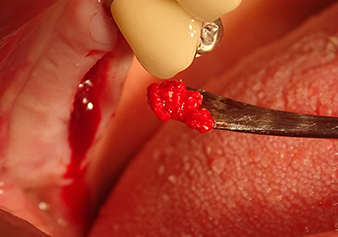

Lo scollatore viene utilizzato per posizionare con cura della miscela per il rialzo nella regione dell'ostio interno del seno mascellare in direzione apicale

Fig.8: lo scollatore viene utilizzato per posizionare con cura della miscela per il rialzo nella regione dell'ostio interno del seno mascellare in direzione apicale.